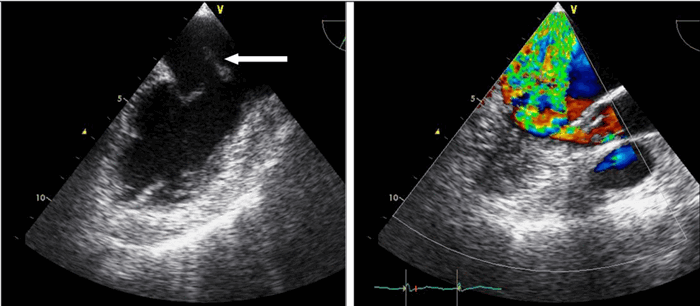

Несмотря на принимаемые меры лечения, состояние пациентки оставалось тяжелым, на фоне кардиогенного шока отмечались признаки острого почечного повреждения (скорость клубочковой фильтрации составила 17 мл/мин/1,73 м 2 ), острой энцефалопатии. По данным трансторакальной эхокардиографии (ЭхоКГ) сердца (табл. 1) на фоне акинеза среднего и апикального сегментов межжелудочковой перегородки, передней и боковой стенок левого желудочка (ЛЖ) с захватом верхушки ЛЖ, отмечалась сепарация листков перикарда в диастолу — 1,2 см за задней и боковой стенками ЛЖ, у верхушки — 0,8 см за счет наружного разрыва миокарда. Вся полость перикарда заполнена отложениями фибрина умеренной эхогенности. В области верхушки со стороны полости ЛЖ лоцировался дополнительный эхосигнал (пристеночный тромб) размером 2,7х1,6 см, под которым визуализировалось эхонегативное пространство размером 1,6х0,9 см (место разрыва миокарда) (рис. 4, 5). Кровоток через место разрыва миокарда не определялся.

Рис. 4. Трансторакальная ЭхоКГ пациентки Б.

Примечание: апикальная 2-х камерная позиция: сепарация листков перикарда в диастолу — 1,2 см за задней и боковой стенками ЛЖ, у верхушки — 0,8 см за счет наружного разрыва миокарда, под ним эхонегативное пространство размером 1,6х0,9 см (место разрыва миокарда).

Сокращение: ЛЖ — левый желудочек.